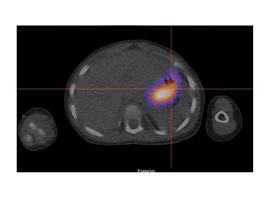

La scintigraphie au Pertechnétate de Tc99m est le test de choix pour identifier la muqueuse gastrique ectopique chez les patients dont la suspicion clinique est élevée. Cependant, quoique le diverticule puisse potentiellement être identifié sur la TDM faible dose si effectuée, s’il n’y pas de muqueuse gastrique ectopique ou cause de faux positif, l’étude scintigraphique par elle-même sera négative. Dans la scintigraphie au 99mTc-Pertechnétate, la captation du traceur est principalement au niveau des cellules sécrétrices de mucine mais son élimination est influencée par les cellules pariétales11,12. Sans manipulation pharmacologique, il y a élution du traceur de l’estomac vers le duodénum et le grêle en cours d’étude. Il est également visualisé l’élimination physiologique par les reins vers la vessie (figure 1 ).

Figure 1 : Examen effectué sans préparation pharmacologique et avec SPECT simple chez un patient de 4 ans avec rectorragies. Mise en évidence d’une élution du traceur en cours d’étude avec visualisation du duodénum et du grêle. Acquisition dynamique ( A ), cliché statique à 30 minutes post injection (B) et rendu 3D de l’acquisition tomographique (C)